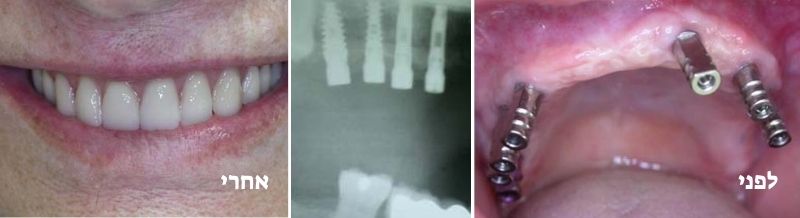

מקרה 1:

שתלים ותותבות על שתלים

מקרה 2:

תותבות על שתלים עם מחברים כדוריים או לוקייטורים